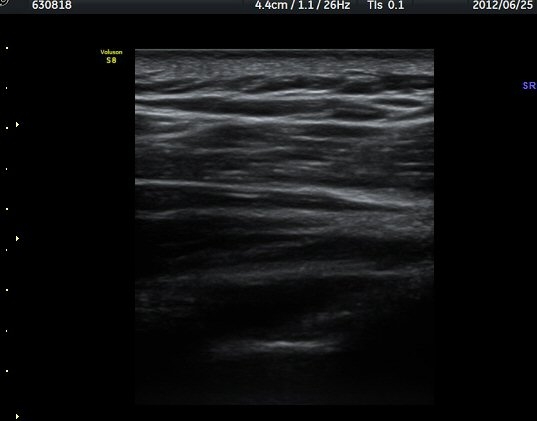

ÃÊÀ½ÆÄ °Ë»ç

¾î±ú °üÀý µÚÂÊ ÈĹæ°üÀý¼ø Ⱦ´Ü¸é°Ë»ç¿¡¼­ °üÀý¼ø ³»Ãø, °¡½Ãµ¹±â°üÀý¼ø°í¶û(spinoglenoid

notch)¿¡¼­ Àú¿¡ÄÚ ³¶Á¾ÀÌ °üÂûµÈ´Ù(±×¸² 1). ŽÃËÀÚ¸¦ À§-¾Æ·¡ ¹æÇâÀ¸·Î º¯°æÇÏ¿© °üÂûÇÒ ¶§µµ

¿ª½Ã °ß°©°ñ °¡½Ãµ¹±â(spine) ¾Æ·¡¿¡¼­ Àú¿¡ÄÚ ³¶Á¾ÀÌ °üÂûµÈ´Ù(±×¸² 2). º¼·ÏŽÃËÀÚ·Î ¹Ù²Ù¾î °ü

ÂûÇÏ´Ï  °¡½Ãµ¹±â°üÀý¼ø°í¶û¿¡¼­ Àú¿¡ÄÚ ³¶Á¾ÀÌ ´õ¿í ¶Ñ·ÈÈ÷ °üÂûµÈ´Ù(±×¸² 3, 4).